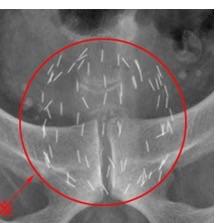

そんな中で、小泉源の留置の仕方に技量が出てくると話があり、簡単に言うと、直線的な配置では治療の効果が得られず、栗の形をした前立腺に沿って曲線的に留置することが大事だと。O先生の前立腺癌の治療に対する情熱、技量にここで最良の治療を受けることができ良かったと思います。年末に同病の友人を紹介しましたが、O先生の治療を待っている患者さんが100人を超えるようです。